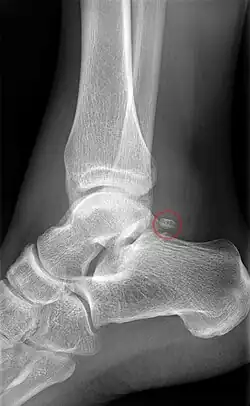

Beim Röntgen ist das Os trigonum als dreieckiges, rundes oder ovales Gebilde am Processus posterior tali bei seitlicher Aufnahme am besten zu erkennen. In den meisten Fällen ist es ein einzelner Knochen, es können aber auch mehrere Os trigonum ausgebildet sein.